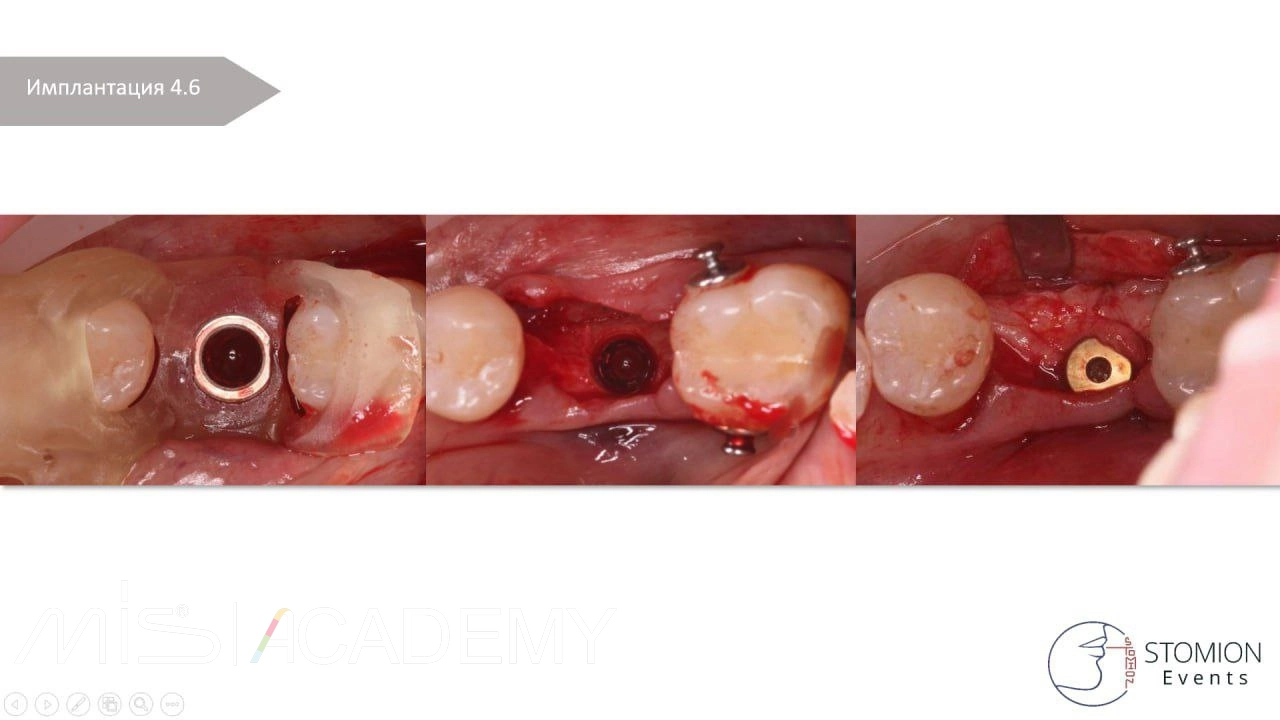

— 4.6 имплантация MIS C1 3,75х10 + connect 2мм + СТТ, фиксированный апикально к надкостнице, перекрыт расщепленным лоскутом.

— 3.7 удаление, одномоментная имплантация в перегородку, MIS C1 4,2×13 + connect 2мм, в лунки Bio-Oss S + A-PRF + немедленная нагрузка.

Контроль сразу после операции, далее 2-3-4 года.